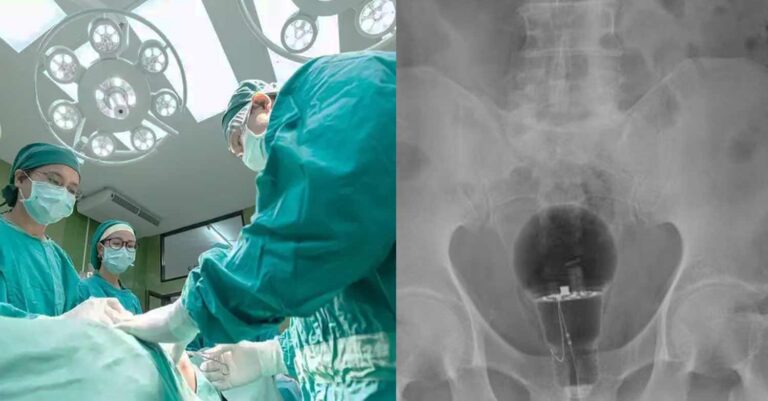

Άναυδοι έμειναν οι γιατροί σε νοσοκομείο της Κολομβίας, όταν διαπίστωσαν πως μια λάμπα βρισκόταν μέσα στον πρωκτό ενός ασθενή, 53 ετών.

Ο ασθενής, ο οποίος δεν έχει κατονομαστεί, πήγε φέτος σε τοπικό νοσοκομείο παραπονούμενος για πόνο στο σημείο. Οι γιατροί δεν είδαν τίποτα κατά τη διάρκεια της φυσικής εξέτασης, αλλά σοκαρίστηκαν όταν μια ακτινογραφία αποκάλυψε μια μεγάλη λάμπα σφηνωμένη, σύμφωνα με τη Daily Mail.

ezgif 1 e84489c476

Δεν ήταν σαφές πώς βρέθηκε εκεί ο λαμπτήρας. Δεν ήταν επίσης σαφές πώς αφαιρέθηκε ο λαμπτήρας ή αν το άτομο υπέστη μακροχρόνια βλάβη. Οι γιατροί δήλωσαν ότι ο ασθενής ήταν τυχερός που η λάμπα δεν είχε σπάσει.